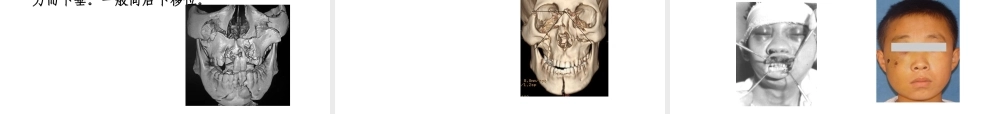

颌骨骨折颌骨骨折一、内容一、内容复习上、下颌骨的解剖特点复习上、下颌骨的解剖特点掌握上、下颌骨骨折的临床症状以及掌握上、下颌骨骨折的临床症状以及上颌骨骨折的分类和下颌骨骨折的好上颌骨骨折的分类和下颌骨骨折的好发部位发部位掌握上、下颌骨骨折的治疗原则和常掌握上、下颌骨骨折的治疗原则和常用固定方法用固定方法三、解剖特点三、解剖特点上颌骨上颌骨(maxilla)(maxilla)解剖结构解剖结构上颌骨结构特点上颌骨结构特点上颌窦支柱及支架结构上颌骨主要以表情肌附着上颌骨血液供应极为丰富支柱及支架结构支柱及支架结构垂直的支柱结构垂直的支柱结构•鼻上颌支柱•颧上颌支柱•翼上颌支柱支柱及支架结构支柱及支架结构水平的支架结构水平的支架结构•牙弓•眶下缘•眶上缘•颧骨颧弓下颌骨下颌骨(mandible)(mandible)结构特点结构特点水平部(下颌体)垂直部(下颌支)下颌骨内部结构下颌骨内部结构下颌管内有下牙槽神经血管束。骨皮质较厚下颌骨骨折好发部位下颌骨骨折好发部位正中联合(颏正中)颏旁区下颌角髁突颈部血液供应血液供应主要来自下牙槽动脉,同时还接受周围软组织的血液供应。上、下颌骨骨折的临床的共性表现上、下颌骨骨折的临床的共性表现外伤病史局部肿胀局部疼痛局部出血骨块移位咬合错乱功能障碍异常动度上颌骨骨折(fracturesofthemaxilla)1.1.骨折线骨折线LeFort按骨折线的高低位置,将其分为三型。LeFortLeFortⅠⅠ型骨折(低位骨折)型骨折(低位骨折)由梨状孔下方,牙槽突上方(基部)向两侧水平后延之上颌翼突缝。LeFortLeFortⅡⅡ型骨折(中位骨折、锥型骨折(中位骨折、锥形骨折)形骨折)由鼻额缝向两侧横过鼻梁、眶内侧壁、眶底、颧上颌缝,再由上颌骨侧壁至翼突。可合并颅脑损伤、脑脊液漏。LeFortLeFortⅢⅢ型骨折(高位骨折、颅型骨折(高位骨折、颅面分离骨折)面分离骨折)由鼻额缝向两侧横过鼻梁、眶部、经颧额缝后至翼突。表现为颅面分离、可合并颅脑损伤、耳鼻出血或脑脊液漏。上颌骨骨折(上颌骨骨折(LeFortⅠⅡⅢLeFortⅠⅡⅢ型)型)上颌骨矢状骨折上颌骨牙槽突骨折上颌骨骨折的临床表现2.2.骨折块移位骨折块移位骨折块多随外力的方向而移位,或因重力而下垂。一般向后下移位。上颌骨骨折的临床表现3.3.咬合关系错乱咬合关系错乱上颌骨块的移位必然引起咬合错乱,若一侧上颌骨下移较多,该侧就出现咬合早接触。上颌骨骨折的临床表现4.4.眶及眶周...